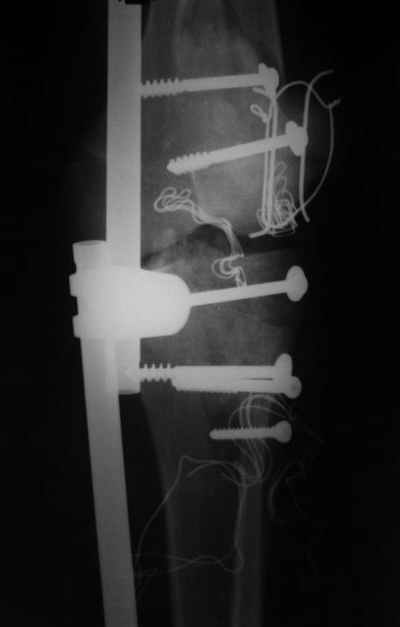

Спасибо за комментарии. Травма тяжелая с проблематичным прогнозом для функции коленного сустава( изначально травма разгибательного аппарата с последующим частичным некрозом собственной связки надколенника и о обнажением рефиксированного фрагмента бугристости большеберцовой кости, дефектом центрального отдела суставной поверхности большеберцовой кости и медиального отдела капсулы сустава).